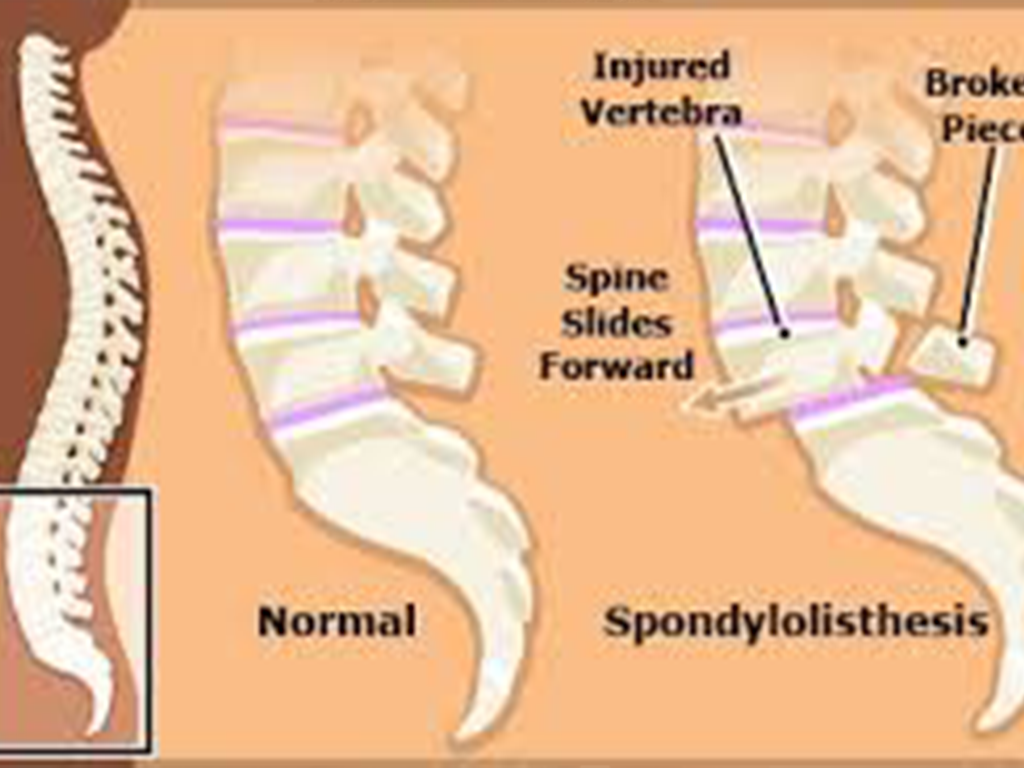

Lumbar Spondylolisthesis is a spinal condition where one of the vertebrae in the lower back (lumbar spine) slips forward over the vertebra beneath it. This misalignment can cause lower back pain, stiffness, nerve compression, and sometimes leg pain or weakness.

It commonly affects the L4-L5 and L5-S1 levels and can range from mild to severe based on the degree of slippage

Age-related degeneration of discs and joints

Repetitive stress from sports or heavy lifting

Spinal trauma or fractures

Congenital defects

Spinal tumors or infections

Post-surgical instability